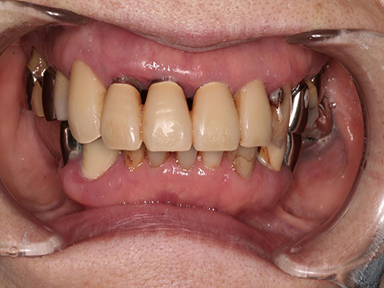

治療後口腔内写真